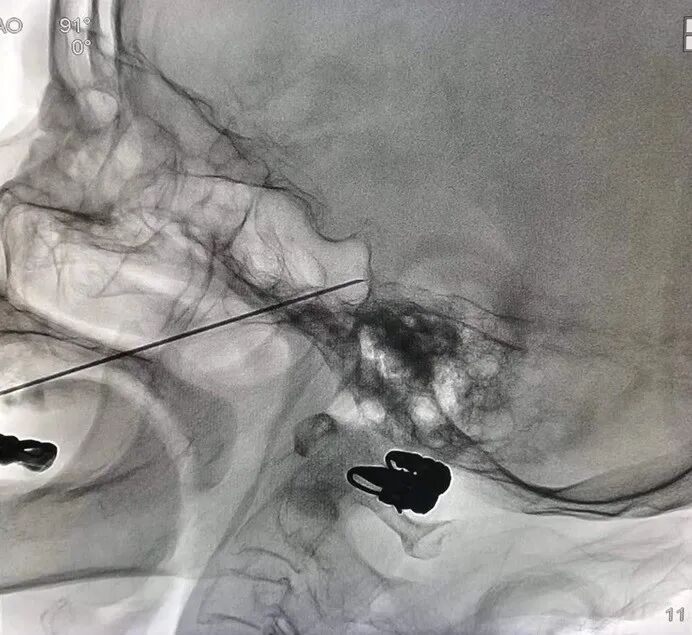

谢河秋主任对程女士进行了详细检查和会诊,诊断为原发性三叉神经痛。在术前检查完善后即为程女士进行三叉神经半月节射频毁损术,手术台上,程女士就觉得疼痛瞬间消失,术后第2天就出院了。

据了解,三叉神经半月节射频毁损术是医生在CT或C臂提供的 “慧眼”下,精确地把一根细针通过面部穿刺到颅底部的三叉神经的“老根”(半月神经节)进行射频治疗。术后疼痛很快消失,多数患者术后第2天即可出院,总住院疗程3-4天。